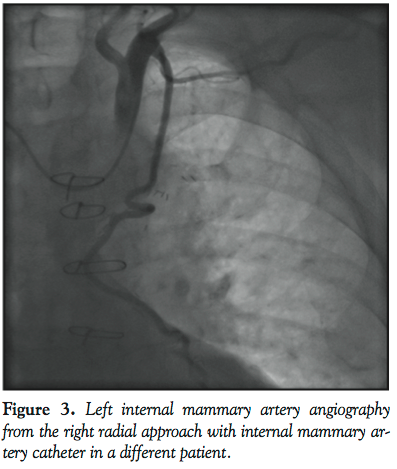

The patient is a 70-year-old man who had 4-vessel CABG in 1998 with LIMA to LAD, sequential saphenous vein graft (SVG) to diagonal artery and obtuse marginal artery, and SVG to posterior descending artery. He was transferred to our institution for management of common hepatic duct injury and biliary leak secondary to iatrogenic injury from a cholecystectomy operation. The patient had episodes of hypotension that were associated with ischemic changes on electrocardiogram and elevated troponins. He was referred for cardiac catheterization for non-ST elevation myocardial infarction. The patient has severe peripheral vascular disease and both femoral arteries had been bypassed surgically. The left radial artery had an arterial line already in place. Due to limited vascular access, the right radial artery was chosen as the access route. A 5 Fr arterial sheath was inserted into the right radial artery using standard technique. A 5 Fr Optitorque Radial TIG 4.0 catheter (Terumo Medical Corporation) was advanced over a 0.035˝ Versacore guidewire (Abbott Vascular) to the ascending aorta. The catheter was used to engage the left coronary artery first (Figure 1A). The LAD was occluded. The ramus intermedius had moderate disease proximally, and a jump graft from the ramus to the diagonal artery was seen. There was no retrograde flow of this graft beyond the diagonal artery anastomosis. The circumflex artery was patent. After left coronary angiography, the catheter was disengaged and manipulated to engage the right coronary artery (RCA) (Figure 1B). The RCA was occluded in its mid-portion. After right coronary angiography, the catheter was disengaged and pulled higher up the aorta and the SVG to the PDA was engaged (Figure 1C). This SVG was widely patent. The catheter was disengaged from the SVG and the Versacore wire was manipulated into the descending aorta after pulling back and rotating the catheter. The catheter was advanced past the origin of the left subclavian artery. The wire was removed and the catheter was retracted back with the tip pointing in the cranial direction and the left subclavian artery was engaged (Figure 1D). The Versacore wire was then advanced into the left subclavian artery and manipulated down the left arm. Over the wire, the TIG catheter was advanced past the LIMA. The wire was removed and the catheter was pulled back and torqued to semi-selectively engage the LIMA. LIMA angiography was performed, and showed the LIMA to be widely patent (Figure 2). The catheter was then removed over a guidewire. The etiology of the elevated troponins was deemed to be from demand ischemia from biliary sepsis and hypotension. A TR Band (Terumo Medical Corporation) was used to obtain hemostasis after sheath removal.

The last hurdle is to engage the LIMA for adequate angiography. Cha et al reported that selective LIMA angiography via right radial access was successfully performed in 164 out of 184 patients (89%) using a 5 Fr modified Simmons catheter. This technique, however, requires reshaping of the catheter. Alternatively, Tai reports that LIMA angiography can be successfully performed with the left coronary bypass (LCB) catheter.6 JL1 and IMA catheters have also been successfully used for LIMA cannulation (Figure 3). When selective engagement is not possible, contrast injection with a blood pressure cuff inflated on the left arm often will allow for adequate LIMA opacification.